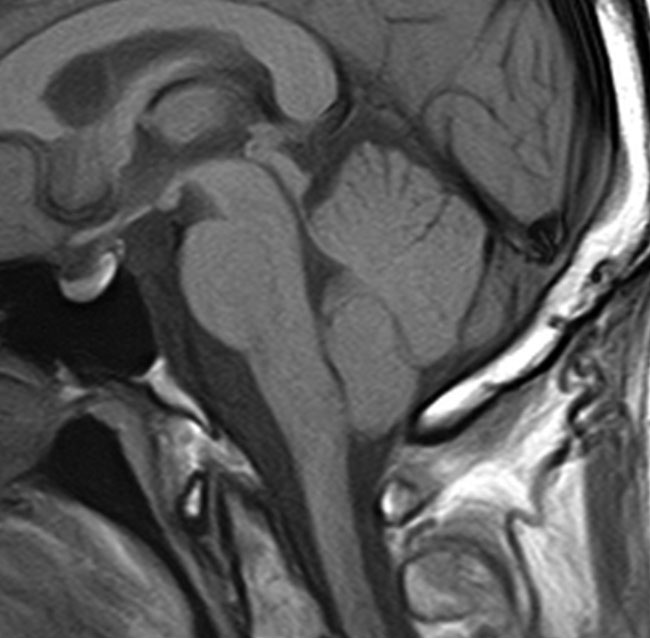

典型的な神経腸嚢胞 neurenteric cyst

左のT2強調画像で等信号,中のT2*で高信号,右はCISS画像です。

T1強調画像では,のう胞周囲の高信号の部分は半固体で,中心部の高信号はドロドロの粘液でした。基本的にガドリニウム増強はされません。まれに薄い膜状に一部が増強されることがあります。

境界明瞭は袋状の腫瘍です。椎骨動脈や脳底動脈を包み込むようにふくらんでいます。

左外側後頭下開頭という小さな開頭手術だけで全摘出しました。術後は幸い何の症状も出ていません。この例は脳幹部に食い込まないもので,運良く全摘できたのですが,そうはいかないものもあります。